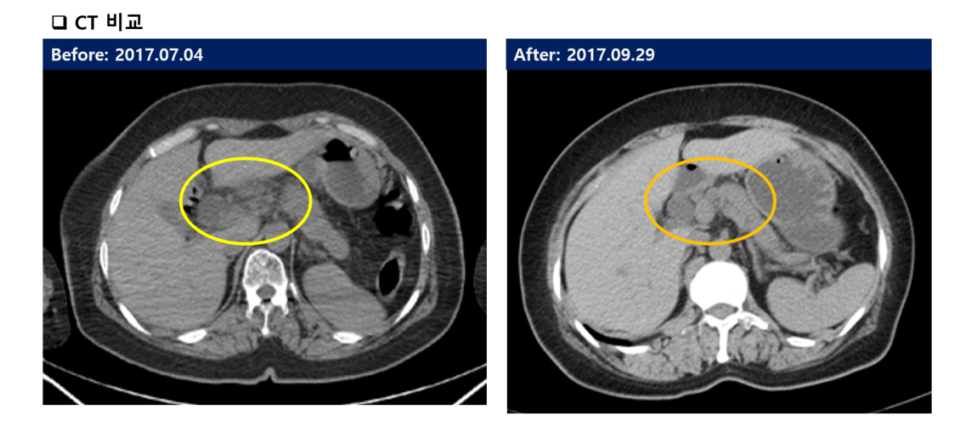

종양 크기는 3.5cm로 꽤 큰 편입니다. 그리고 간 쪽에 혈관종(Hemangioma)도 있었는 환자로 문제는 췌장암세포가 상장간막정맥을 침범하다 보니 수술이 힘들었습니다. 그래서 항암을 시작하여 항암치료와 함께 고용량의 셀레나제 치료와 온열치료 등의 통합의학적 암치료를 2017년 7월부터 시작하였습니다.

▲왼쪽) 췌장 췌부의 암세포에 상장간막정맥이 침범한 모습 ▲오른쪽) 수술 전 분리된 모습

3개월간의 통합의학적 치료 후 췌장암과 상장간막정맥이 분리된 환자분은 수술을 할 수 있게 되었고, 최근 2023년 6월경에 5년 완치판정을 받으셨습니다